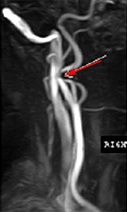

Patológiai zegzugosságát (megtörését) a nyaki artéria egyik legkevésbé megértett és rejtélyes betegség. A szerepe a kóros tekervényességének cerebrovascularis elégtelenség tünete fejlesztés még tanulmányozzák, de úgy találta, hogy az egyik a három halt meg agyvérzés találtak kóros görbék a nyaki vagy a csigolya artériák. A 16-26% a felnőtt lakosság azonosított különböző lehetőségeket hosszabbítás és tekervényességének a nyaki csigolya artériák vagy a nyakon. Megtörését - Ez az egyenetlenség az artéria alkotnak ívek, hurkok és csomók, amelyek befolyásolják a természet véráramlás az artériákban és hozzájárulnak a stroke.

Gubancold mindig fejlődik, mert a kiterjesztése a belső nyaki verőér, amely arra kényszerítette alakul csavarják vagy hurkok. A fölös hossza arteria carotis interna gyakran meghatározott időszakban az embrionális fejlődés, azaz artéria kanyargás gyakran veleszületett. Az életkor, a további szigorítása feleslegben arteria carotis hurok előfordulhat. Egyes kutatók szerint gubancold okozhat neurológiai és mentális problémák a gyermekek óvodai és a korai iskolás korú.

Diagnózis patológiás tekervényességének

Tekintettel a széles körű terjesztése a különböző típusú jogsértések alkotják a nyaki artériák, az orvos-nek pontosan megválaszolni a kérdést -, hogy egy ilyen változás alakja az artéria megtörés vagy nem? A válasz erre a kérdésre lehetővé teszi, hogy meghatározza, hogy szükség van a sebészeti beavatkozást. Diagnosztikai algoritmus alapján a következő séma szerint:

Ha azt állapítjuk meg, hogy a tekervényes artéria felgyorsult áramlás a ponton a hajlító, hogy több, mint 2-szer, ahol a beteg tünetei cerebrovaszkuláris megerősítette érrendszeri elváltozások az agyban anyag oldalán bodros haj, mint hullámok elismert patológiás és figyelemmel a sebészeti korrekciót.